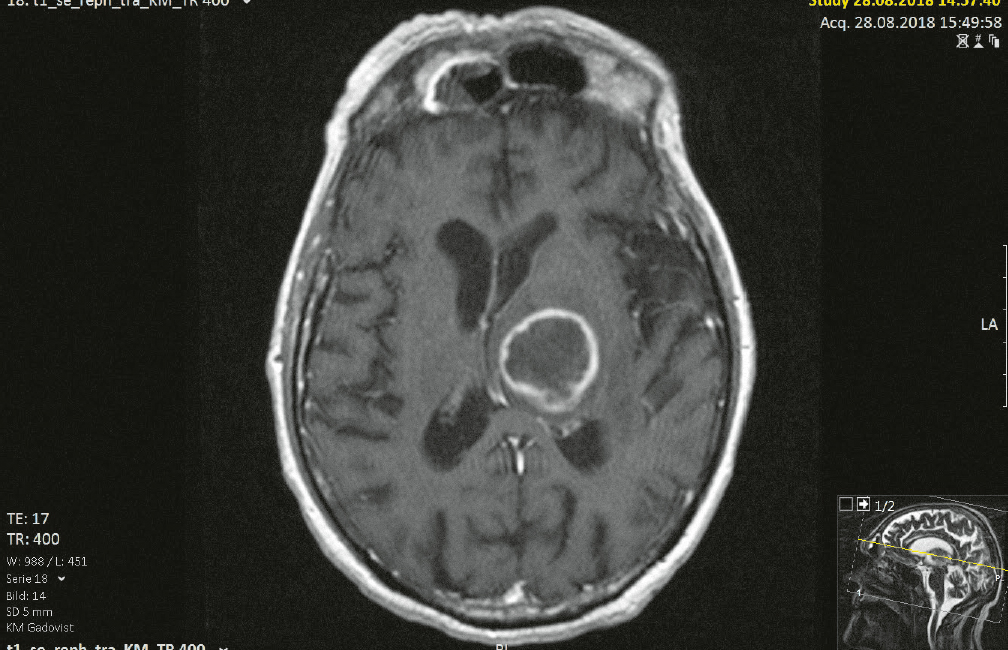

Abb. 10 Patient 4: Magnetresonanztomografie (T2-Gewichtung) eines Patienten, der vom Rettungsdienst somnolent und verwahrlost in seiner Wohnung aufgefunden wurde. Eine primäre Vorstellung fand über die Notaufnahme in der Klinik für Neurochirurgie statt. Es zeigte sich ein Hirnabszess, der im Verlauf chirurgisch entlastet wurde.

Abb. 11 Patient 4: Desolater Zahnstatus des prothetisch und konservierend nicht versorgten Patienten mit multiplen kariösen Zähnen, elongierten Zähnen, Wurzelresten, apikalen Ostitiden. Mit dem Nachweis der Bakterien aus der Streptococcus-anginosus-Gruppe und Fusobacterium nucleatum wurde der Nachweis für eine odontogene Infektion ausgehend von den desolaten, nicht erhaltungswürdigen Zähnen erbracht. Nach Stabilisierung des Patienten erfolgte eine Zahnsanierung.

Tab. 1 Patient 4: Bei der Entlastung des Hirnabszesses wurde ein Abstrich durchgeführt. Mikrobiologisch wurden in der Kultur zahlreiche Bakterien aus der Streptococcus-anginosus-Gruppe (grampositive Aerobier) und Fusobacterium nucleatum (gramnegative Anaerobier) nachgewiesen. Im Antibiogramm zeigten sich die Bakterien aus der Streptococcus-anginosus-Gruppe sensibel gegenüber Penicillin, Ceftriaxon und Clindamycin. Auch Fusobacterium nucleatum zeigte sich sensibel gegen die getesteten Antibiotika.